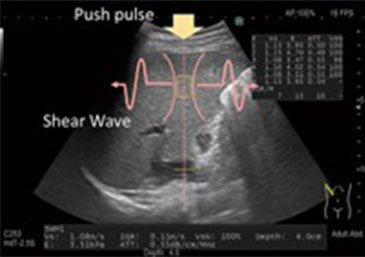

■ 肝線維化診断:肝硬度測定(shear wave)について

プッシュパルスで肝組織を振動させて発生するshear waveの伝搬速度を計測し肝実質の硬さを定量評価します。また別モードのAttenuation Imagingでは脂肪測定も可能です。

通常のエコー検査時に簡便、非侵襲的に検査可能です。脂肪肝のある患者さんには定期的な肝線維化診断(肝硬度測定)をお勧めします。